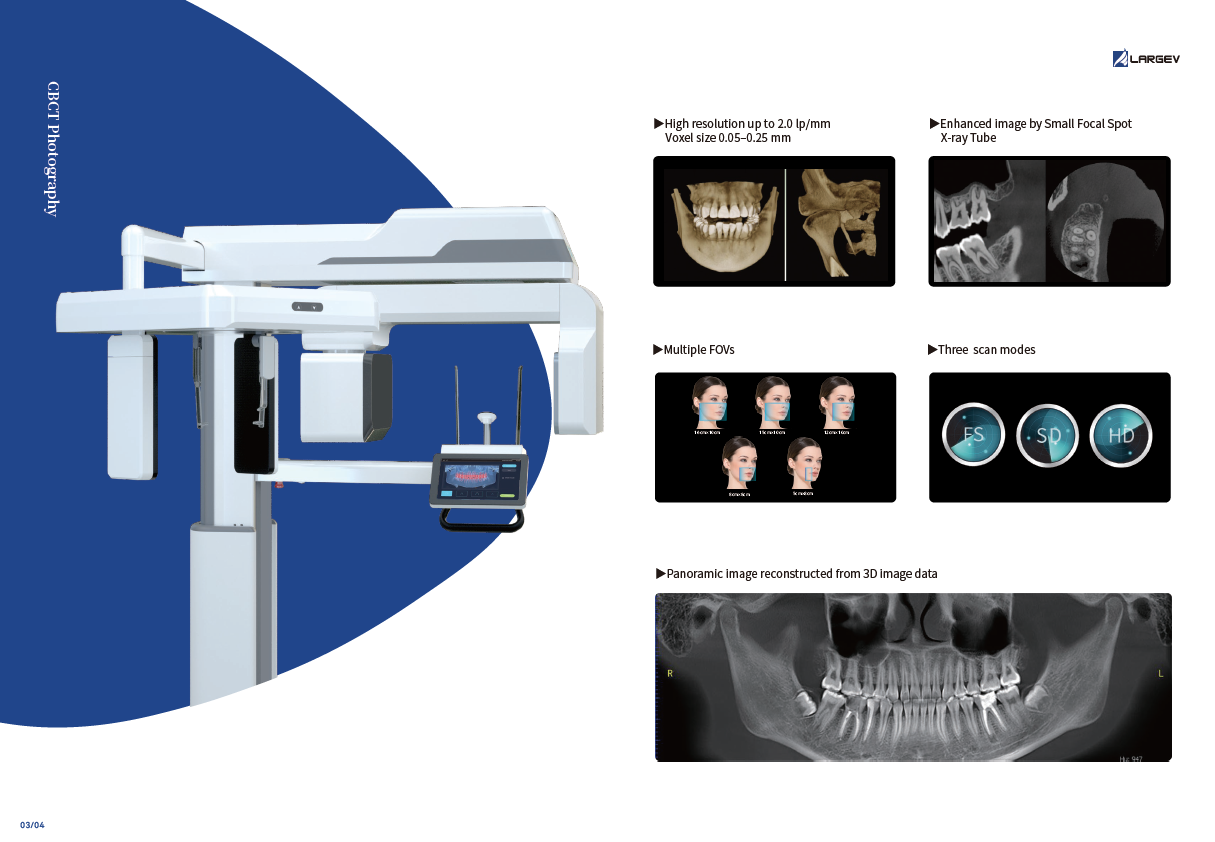

High-Resolution Dental CBCT Imaging

The system achieves image resolutions up to 2.0 lp/mm with a voxel size range of 0.05 – 0.25 mm.

Its 0.5 mm small focus tube guarantees smooth, stable, and reliable scans.

Furthermore, the high-definition image output ensures accurate diagnosis and confident treatment planning.

0.5mm small focus tube ensures outstanding image quality.

Resolution up to 2.0lp/mm, voxel size of 0.25~0.05 mm optional.

Furthermore, Panoramic Images are Reconstructed from 3D Dental CBCT data for clearer visualization

Three Scan Modes of Dental CBCT Imaging System

Additionally, the system provides three flexible scan modes to match clinical needs. Multiple focus layers in panoramic imaging fit each patient’s dental arch perfectly.